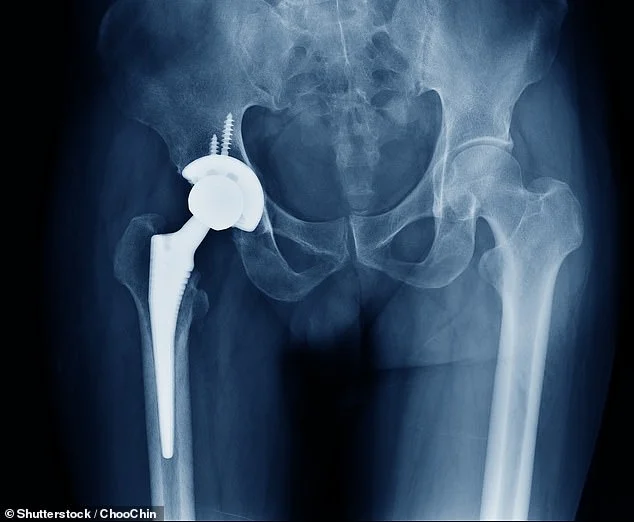

The NHS uses bone cement in 82% of knee replacements and 60% of hip replacements. This material is necessary for about 15,000 operations every month.

Current Supply: Health officials held emergency meetings in February 2026 after discovering only one week of bone cement was left in stock.

The Cause: A shortage of the product, which is made in Germany, has stopped the flow of supplies to the UK.

Official Strategy: Hospitals must now prioritize emergency patients. Those booked for routine joint replacements over the next two months will likely see their dates moved.